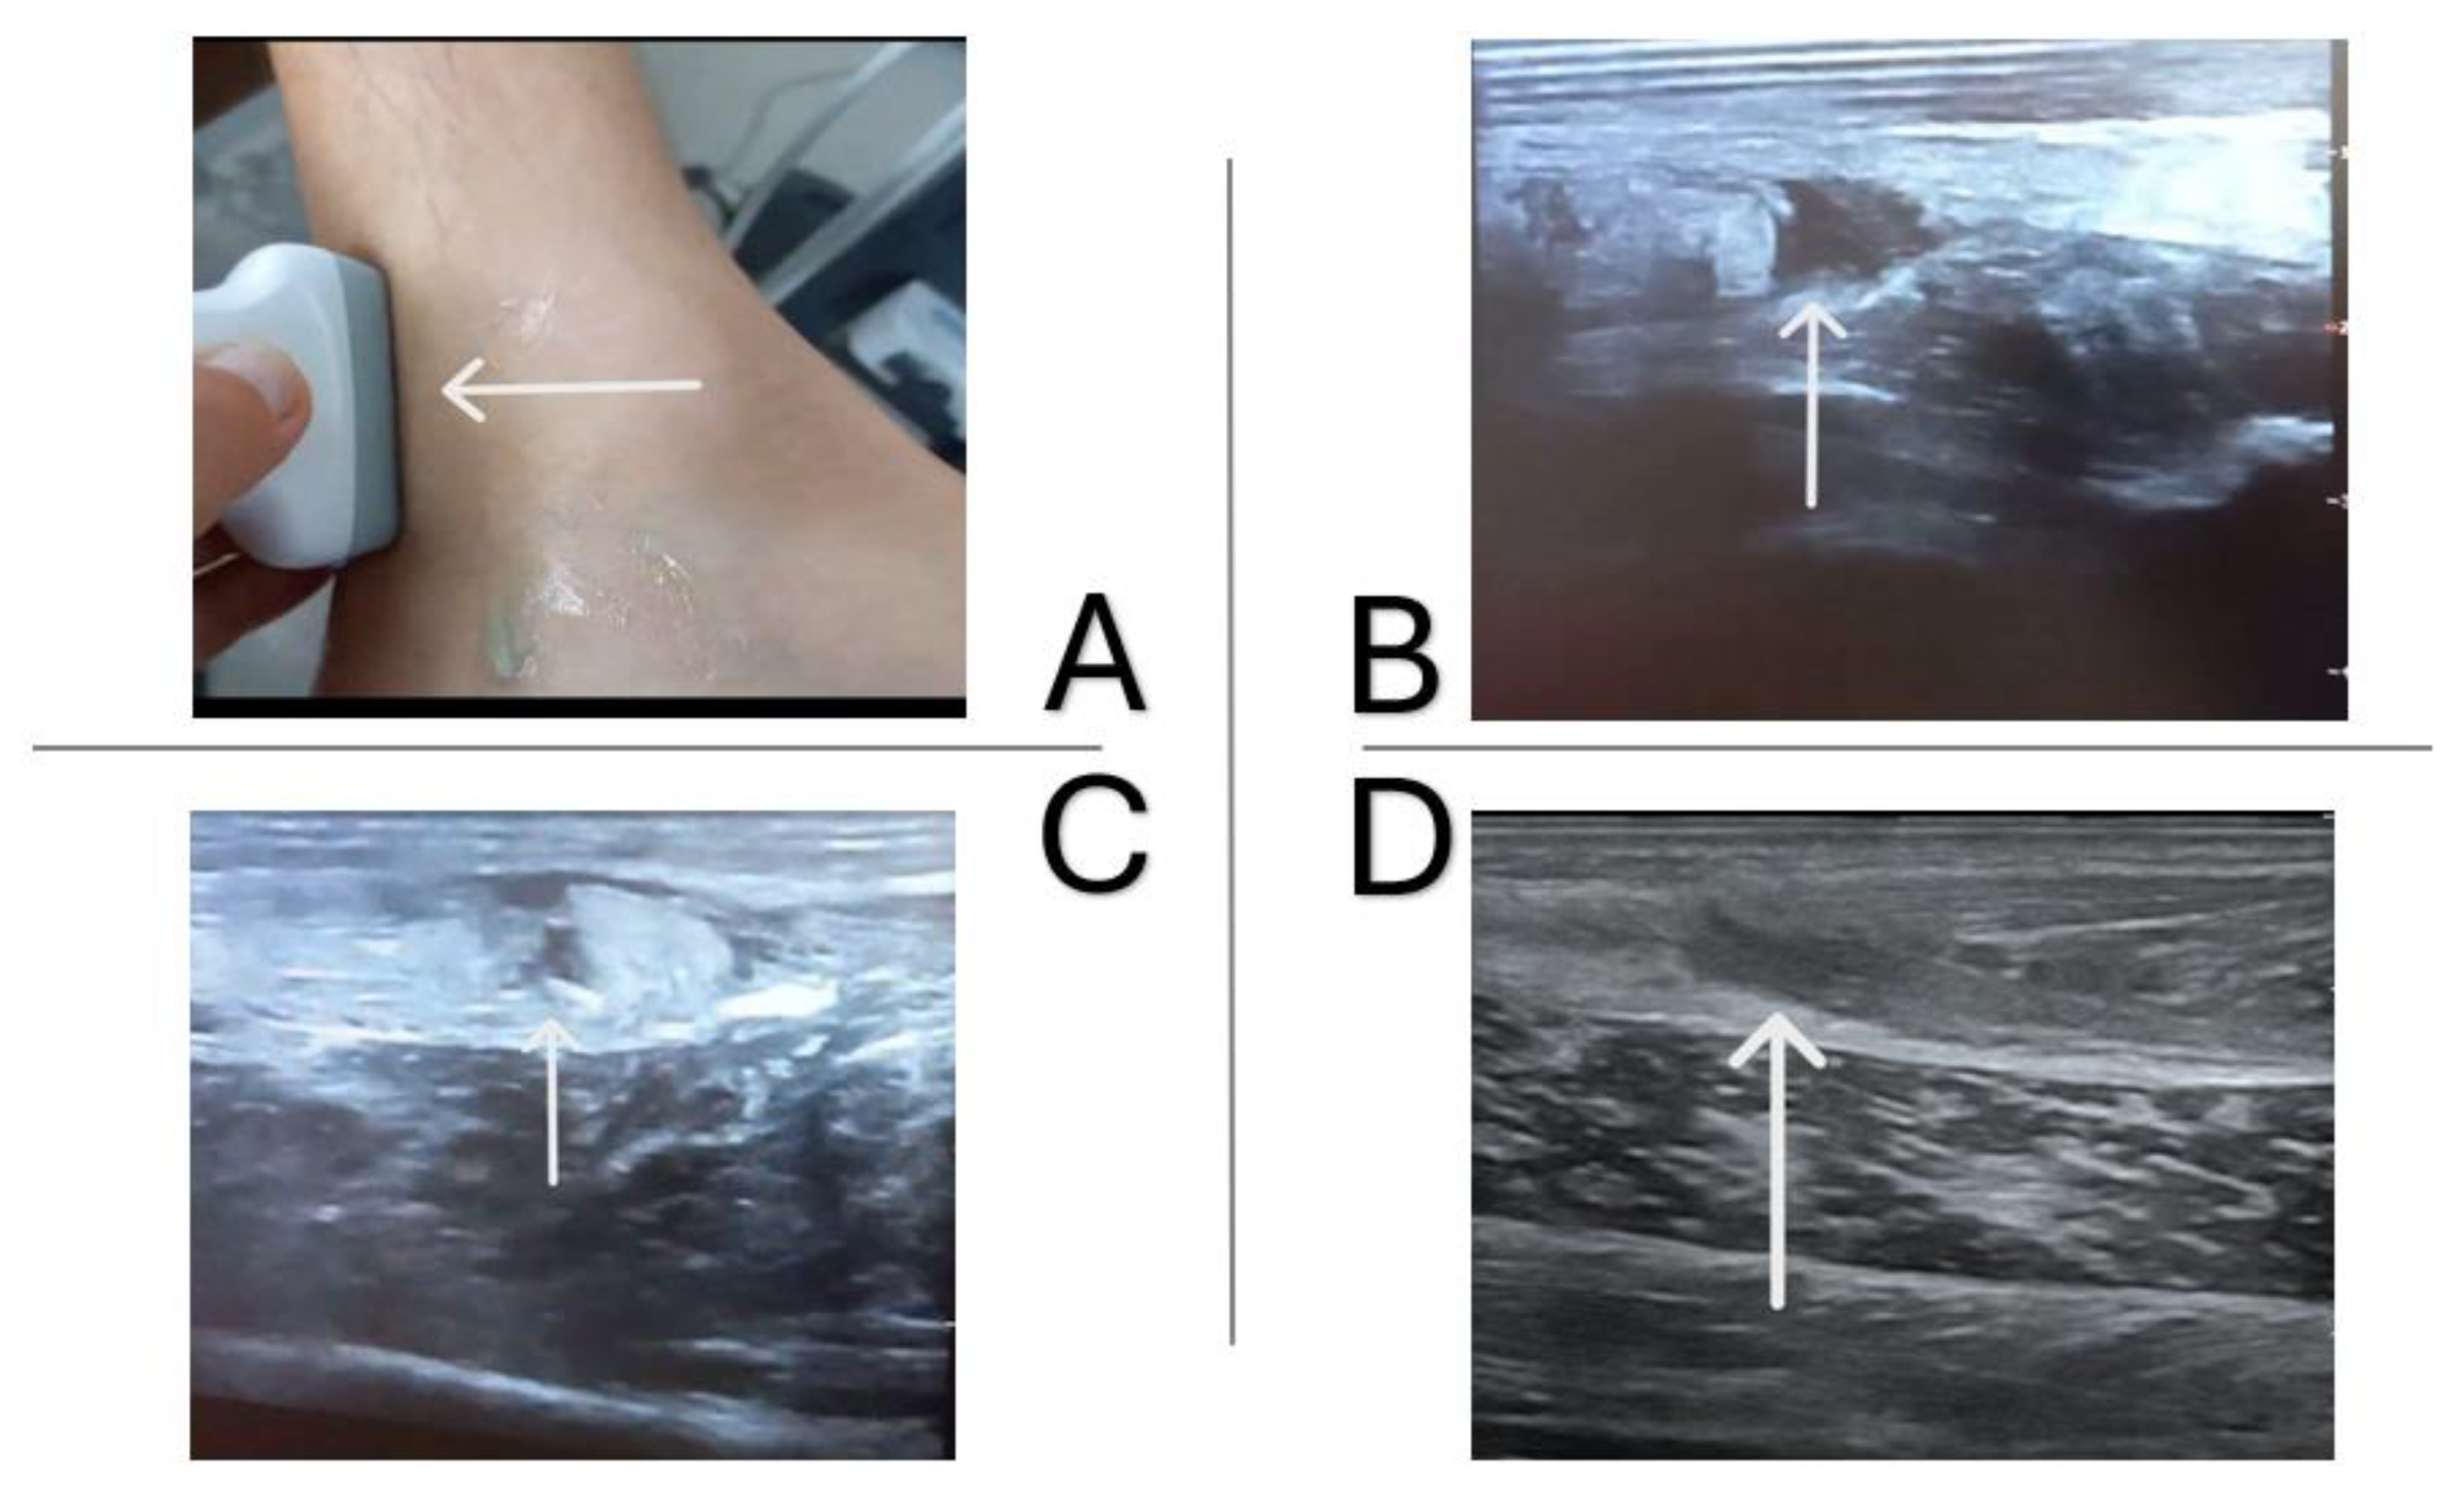

1.4. Case Report

1.5. Imaging Tests